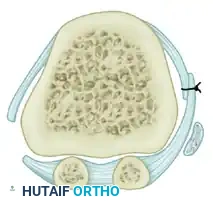

The Modified McBride procedure, refined over decades of orthopedic practice, preserves the fibular sesamoid in the vast majority of cases. It relies on a meticulous lateral soft-tissue release combined with a medial capsulorrhaphy and exostectomy to restore the dynamic balance of the first metatarsophalangeal (MTP) joint. By realigning the deforming forces—specifically the adductor hallucis tendon and the lateral capsule—the procedure centralizes the sesamoid apparatus beneath the first metatarsal head, thereby correcting the hallux valgus deformity without compromising the intrinsic stability of the first ray.

- The main portion of the adductor tendon inserts into the base of the proximal phalanx just plantar to the longitudinal axis of the phalanx. It also possesses a smaller insertion, confluent with the lateral head of the FHB, into the fibular sesamoid.

- Spread the first and second metatarsal heads using a small Inge retractor or a Weitlaner retractor. Holding the adductor tendon under tension greatly facilitates deep exposure. The lateral head of the FHB, the lateral border of the fibular sesamoid, and the conjoined slip of the adductor tendon will come into clear view.

- Sever all attachments of the adductor into its conjoined insertion with the lateral head of the FHB into the fibular sesamoid. When fully released, traction on the adductor should result in free, independent movement without tethering the fibular sesamoid.